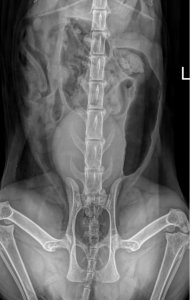

07.12.2021 Bin mit Emily in der TK Beitrag #79 G Gast52809 Gast Röntgenbilder im Normalzustand bis auf den Dickdarm der war noch etwas aufgegast.